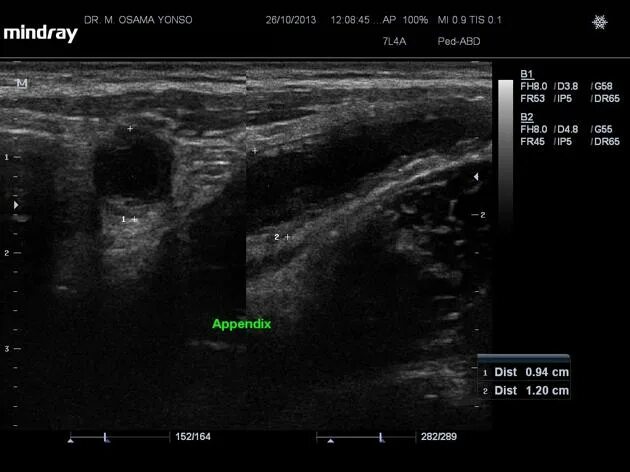

Аппендицит на узи можно ли